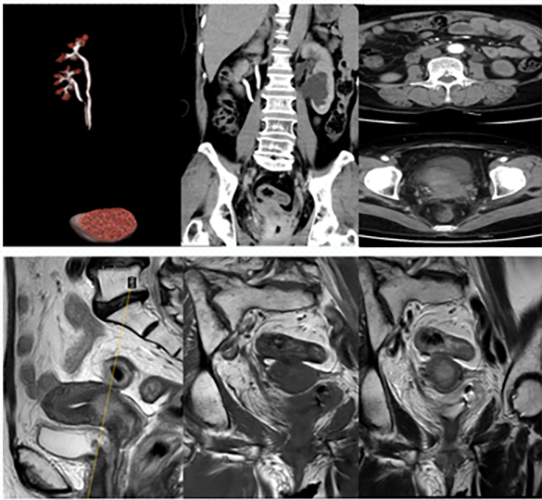

A 56-year-old woman originally diagnosed with squamous cell carcinoma of the cervix stage IIB (FIGO, Federation International of Gynecology and Obstetrics) developed a recurrence 16 months after radical chemoradiotherapy (Fig. 1). She underwent further pelvic exenteration, including ultra radical hysterectomy (Q-M Type D), bilateral adnexectomy, right ureteral stent implantation, left pelvic lymph node dissection, partial cystectomy, total vaginectomy, left internal iliac arteriovenous resection, left pelvic floor muscle resection and left ureteral replantation. In addition, chemotherapy was performed after surgery. Two months after the surgery, she underwent bilateral ureteral stent replacement and left percutaneous nephrolithotomy due to vesicovaginal fistula formation. Bilateral nephrostomy tube replacement was performed due to right nephrostomy tube obstruction. This procedure was done five months after the initial surgery during the patient’s third hospitalization. Unpredictably, the next day, she suddenly had massive intra-abdominal and vaginal bleeding, rapid circulatory disturbances and persistent hemorrhagic shock, which resulted in a rapid drop in hemoglobin from 109 to 48 g/L (reference range 115–150 g/L).

Fig. 1.The cervical canal wall was irregularly thickened with increased 18F-fluorodeoxyglucose (FDG) metabolism and multiple small lymph nodes. At the L3 vertebral level, FDG metabolism was slightly increased in the left para-abdominal aorta and bilateral groin, with the possibility of lymph node metastasis.